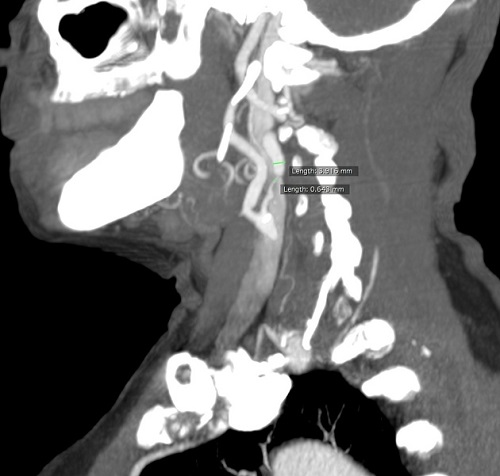

- Stenosis Measurement

North American Symptomatic Carotid Endarterectomy Trial (NASCET): Measures the lumen diameter at the most stenosed segment, then compares with diameter of non-stenosed internal carotid artery more distal (away from head) from the stenosis.

- ICA lumen at the origin < 1.5mm is generally determined as a significant stenosis

Contrast-Enhanced U/S, 3D Ultrasound, Compound Ultrasound, Magnetic Resonance Angiography, Computed Tomography Angiography